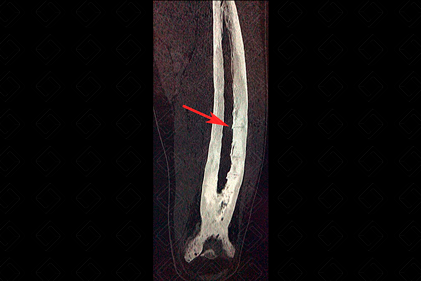

Texto alternativo para a imagem Figura 2. Créditos: Dra. Elazir Mota - Rio de Janeiro/RJ

Texto alternativo para a imagem Figura 3. Créditos: Dra. Elazir Mota - Rio de Janeiro/RJ

Descrição das figuras 2 e 3: Tomografia computadorizada do fêmur do mesmo paciente evidenciando acentuada deformidade óssea. As fraturas horizontais conhecidas como fratura em banana ficaram ainda mais evidentes (seta vermelha).

• Na fase final ou blástica, observam-se áreas de esclerose e aumento do volume ósseo. Nesta última fase da doença, devido à excessiva deposição de osso "anormal", há uma grande predisposição a fraturas, como as características fraturas em banana (figuras 1 e 2). As múltiplas fraturas e o remodelamento ósseo anormal acarretam nas deformidades ósseas. Na calota craniana, há espessamento da tábua interna, levando ao aumento do espaço diploico ( Tam O`Shanter - boina escocesa), podendo acarretar em sintomas neurológicos. Na coluna, o excessivo remodelamento leva ao surgimento da vértebra em marfim , podendo haver aumento volumétrico do corpo vertebral e seus elementos posteriores.